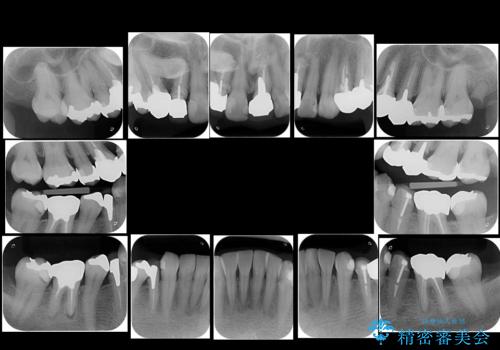

- 銀歯や被せ物のやり替えをご希望で来院。悪いところはすべて治していきたいとのことでした。

根の治療を含めてしっかりやり直しを行いました。